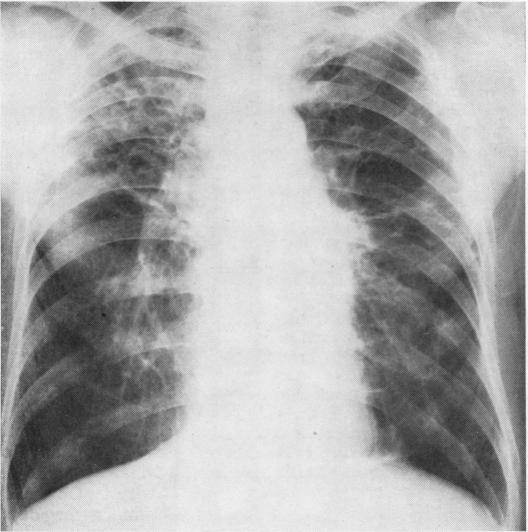

In assessing patients suffering from farmer's lung, the acute stage must be distinguished from the chronic stage of the disease. The conspicuous radiographic signs in the acute farmer's lung episode and the often dramatic clearing make an important contribution to the diagnosis. The radiographic changes in chronic farmer's lung are not specific and cover a wide range of appearances. Even minor nodular changes are significant. Farmer's lung, acute and chronic, is not a disease predominantly characterized by a defect in gas exchange. During the acute illness the reduction in diffusing capacity is often accompanied by a decrease in lung volumes; the pulmonary function profile of the chronic stage is variable. In only a relatively small proportion of chronic farmer's lung patients does a defect in gas exchange predominate, and in some it may be manifest only during exercise. Airway obstruction is a feature of chronic farmer's lung. In chronic farmer's lung patients discrepancies between the severity of complaints and results of pulmonary function tests are not infrequent. In some patients with considerable disability conventional pulmonary function studies may demonstrate little or no impairment of the functions measured. In patients suffering from an acute farmer's lung episode, serological tests should be positive, possibly in high titre. In the chronic stage of the disease the chance of finding positive serology in a patient diminishes with the length of time elapsed since the last acute episode. The period of serological transition appears to be the third year.